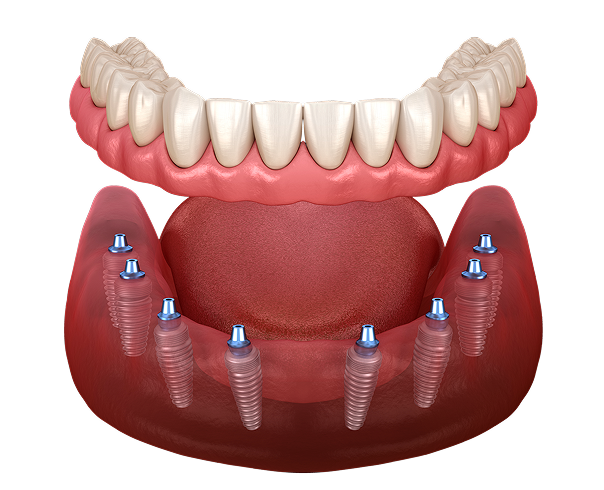

Установка имплантов

Устанавливаем импланты в правильную позицию в костной ткани, чтобы импланты служили максильно долго и не застревала пища между зубами

Сколько имплантов надо ставить на одну челюсть?

4 импланта

• Минимальное количество имплантов

• Бюджетный план лечения

• Без костной пластики

Стоимость под ключ 300 000 ₽

6 имплантов

• Оптимальное количество имплантов

• Хорошая стабильность протеза

Стоимость под ключ 400 000 ₽